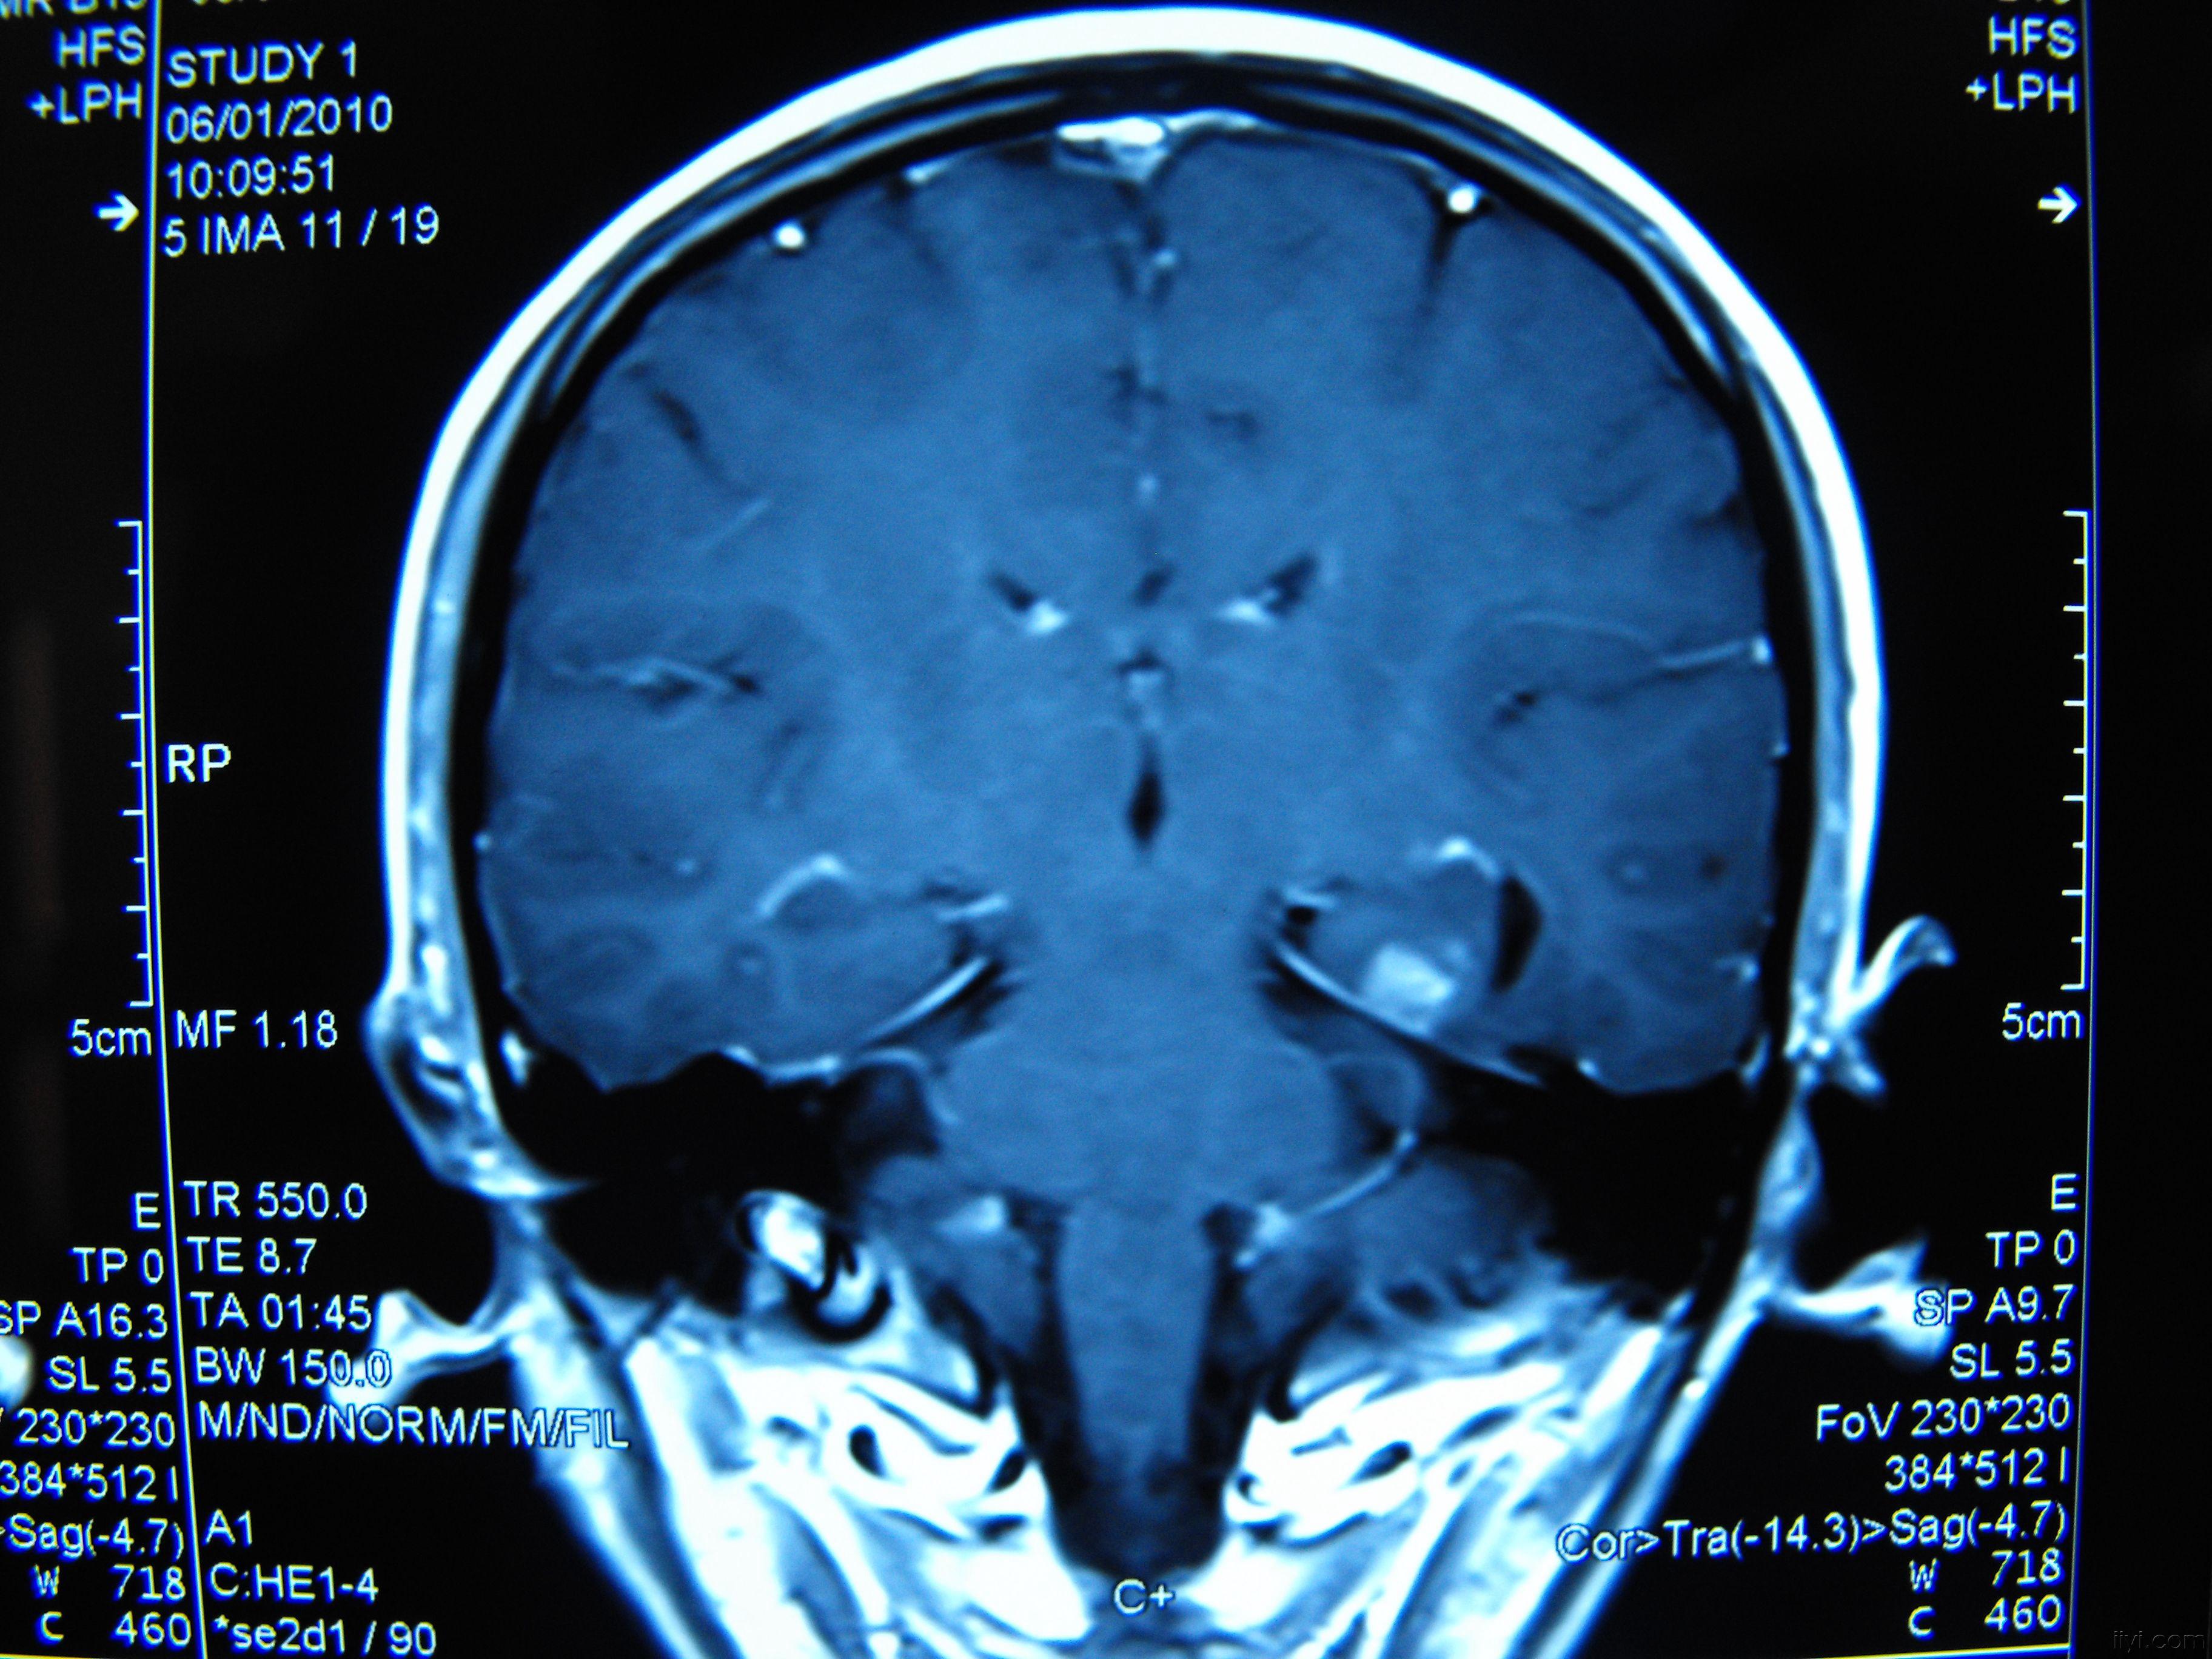

海马区CT

海马硬化的影像诊断

图片尺寸960x720